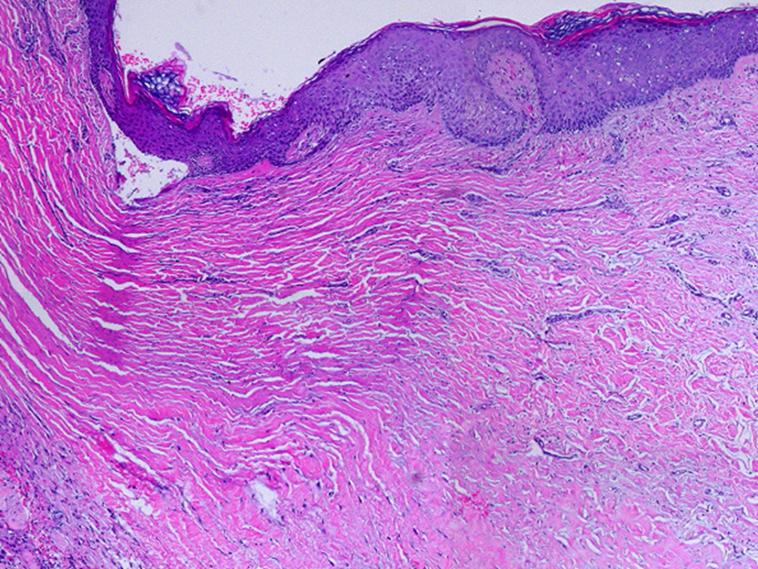

This is a slide showing two distinctly different yet entirely normal events.  On the left is a normal wound module.  On the right is normal Integra.  An original biopsy was taken a week earlier.  The biopsy site, now a normal open wound, developed normal granulation tissue.  The new biopsy was centered on the boundary.  Each half of the image is a completely normal and paradigm demonstration of their own events - normal post-inflammatory wound module, and normal Integra histogenesis.  Absent the matrix, cells follow their normal healing program.  In the presence of the GAG matrix, inflammation-repair is suppressed, and embryonic histogenesis is induced.  Cells, all having the same genotype, remain pluripotential, and can be induced to one reactive program or another depending on inputs.  The histogenesis response never occurs in normal post-parturitional injury and healing, but it can obviously be invoked with the right trigger.

SLIDE SUMMARY:  This is a view of regenerated Integra side-by-side with normal wound healing.  Each half is completely normal and healthy, but the differences are profound - normal wound module versus induced dermatogenesis.

------------------------------------------------------------------------------------------------------------------------------------